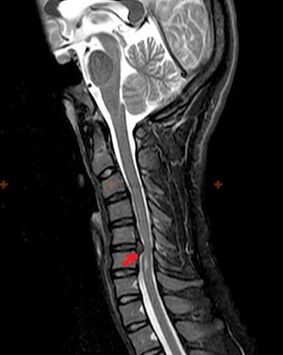

Osteochondrozei diagnozuoti naudojami šie tyrimo metodai: rentgenografija (geriausia su funkciniais tyrimais), MSCT ir MRT. Pastarasis tyrimas yra tinkamiausias dėl to, kad leidžia labai aiškiai įsivaizduoti tarpslankstelinių struktūrų būklę.

Aukščiau aprašytų pokyčių buvimas, taip pat tarpslankstelinio disko struktūros pokyčiai, nustatyti MSCT ir MRT, yra patikimi požymiai, patvirtinantys osteochondrozės buvimą.